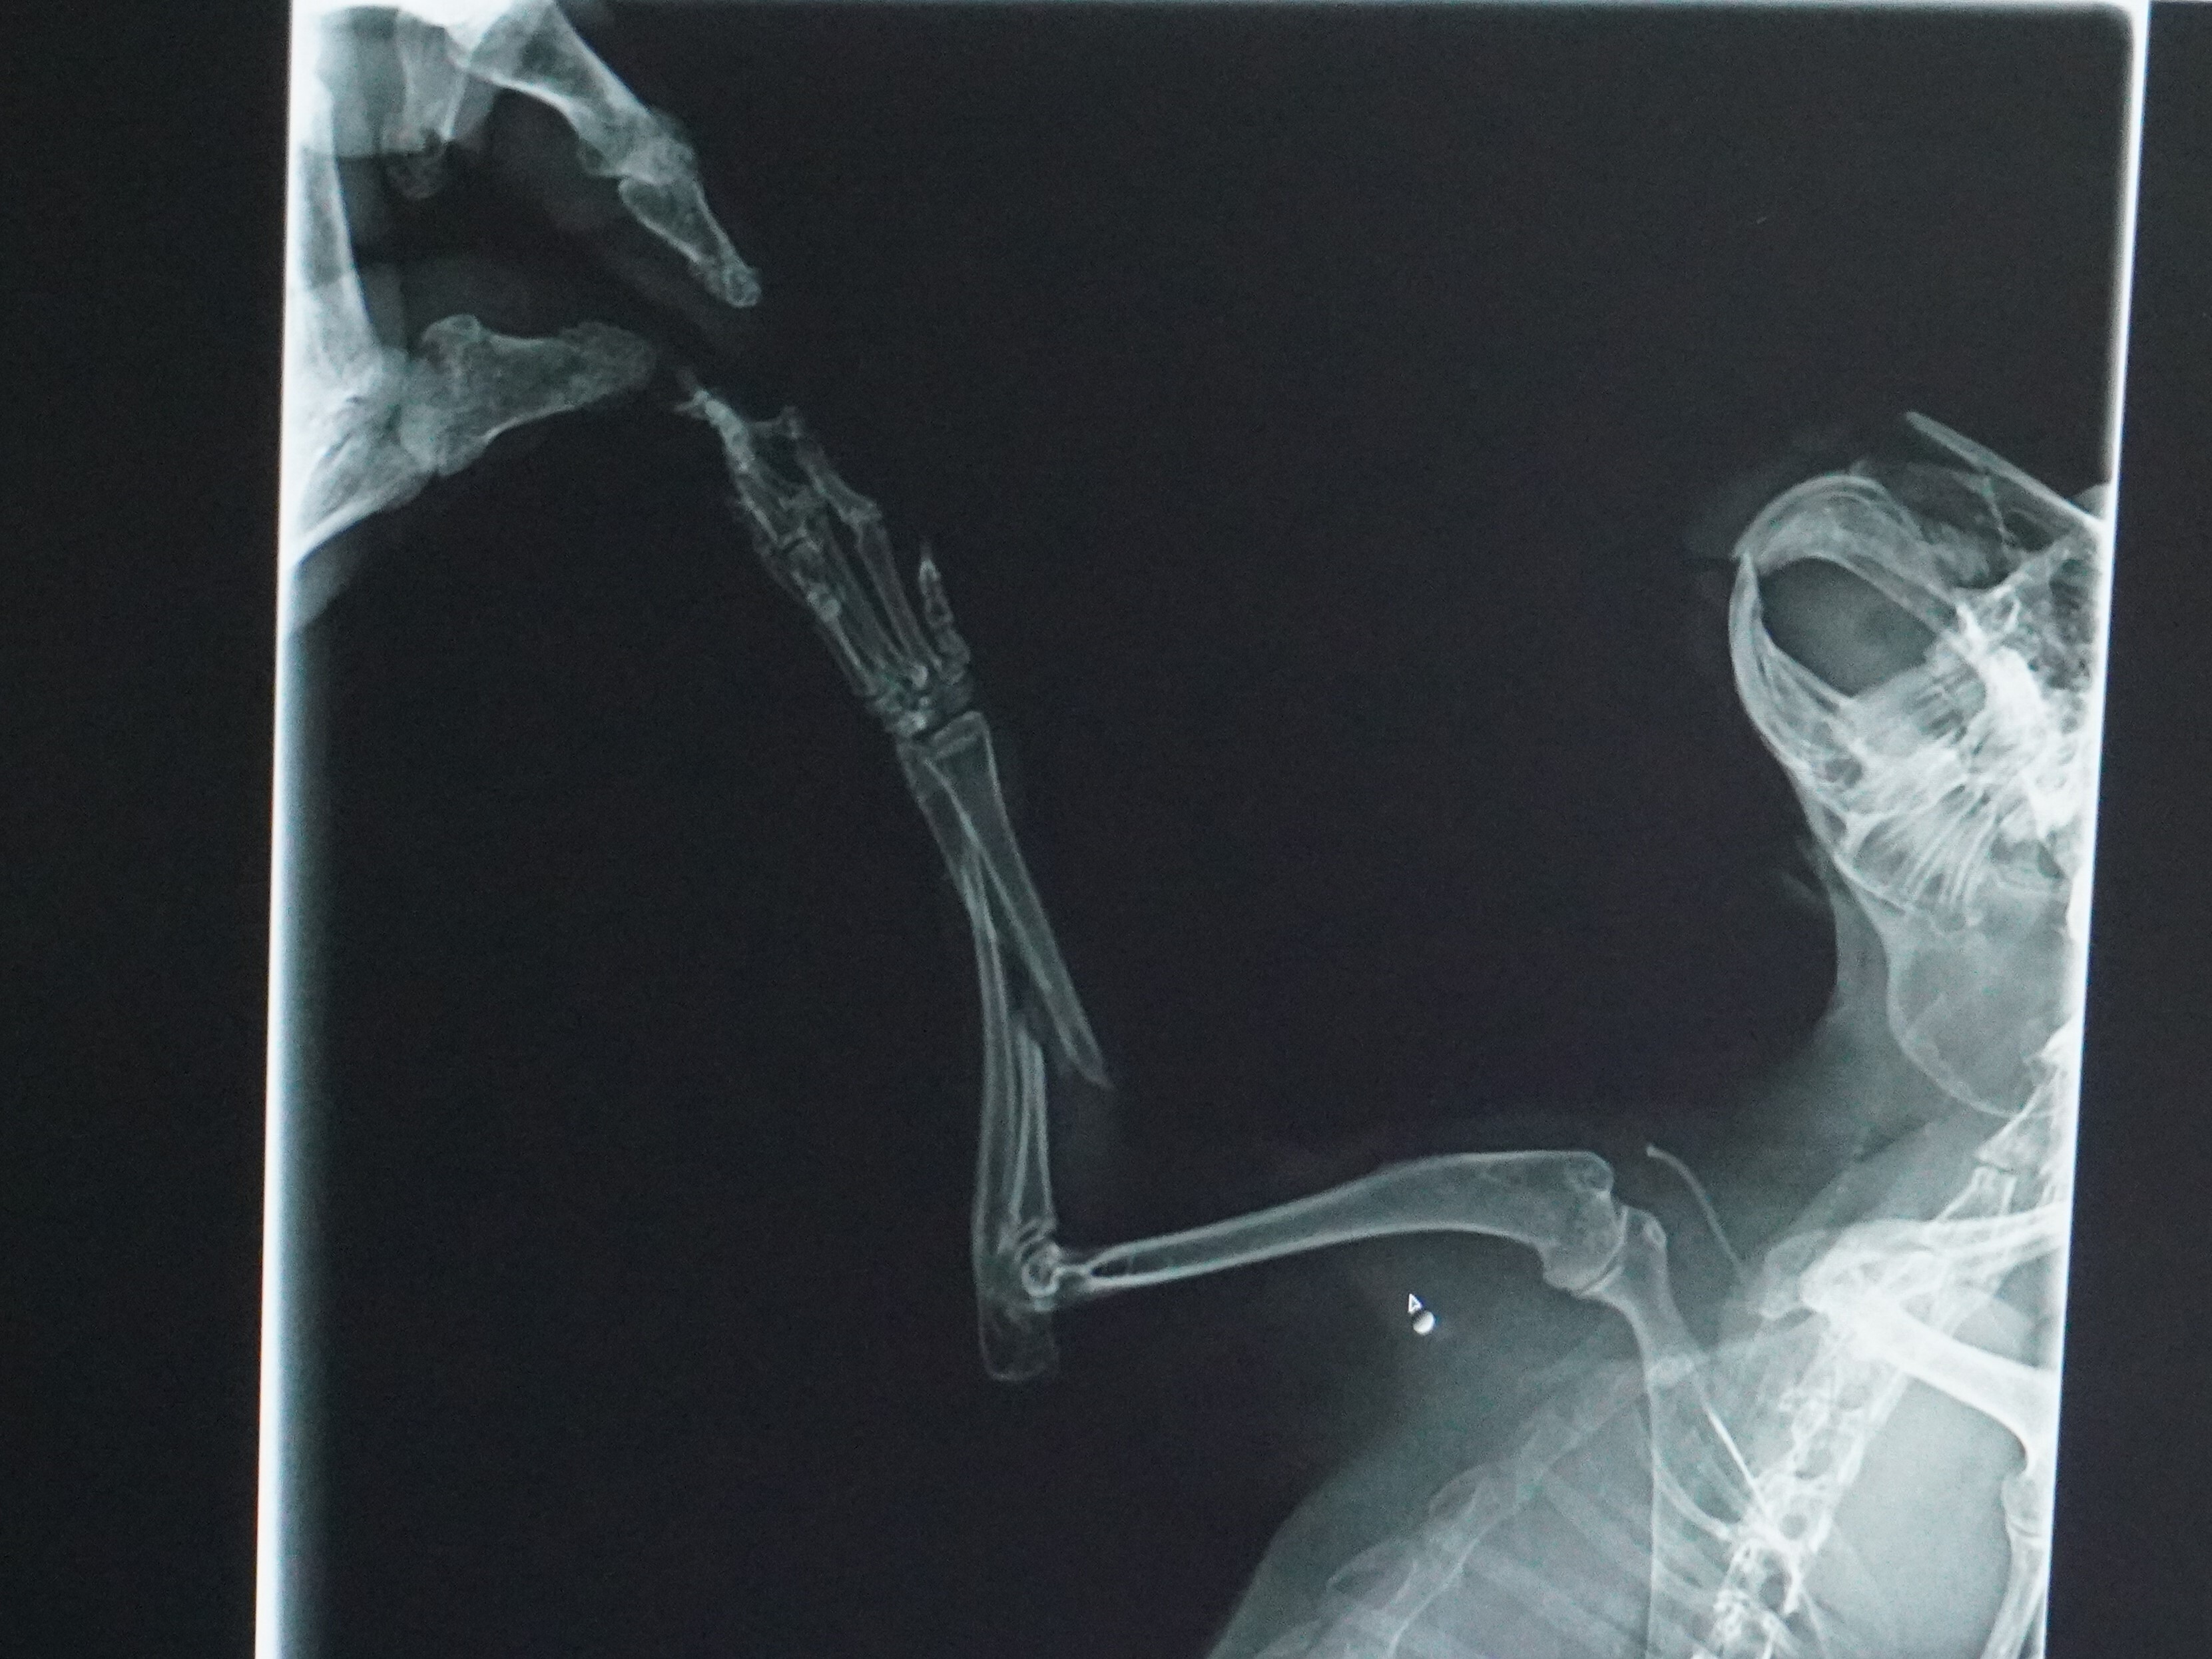

相変わらず、折れた腕は痛そうにしています。